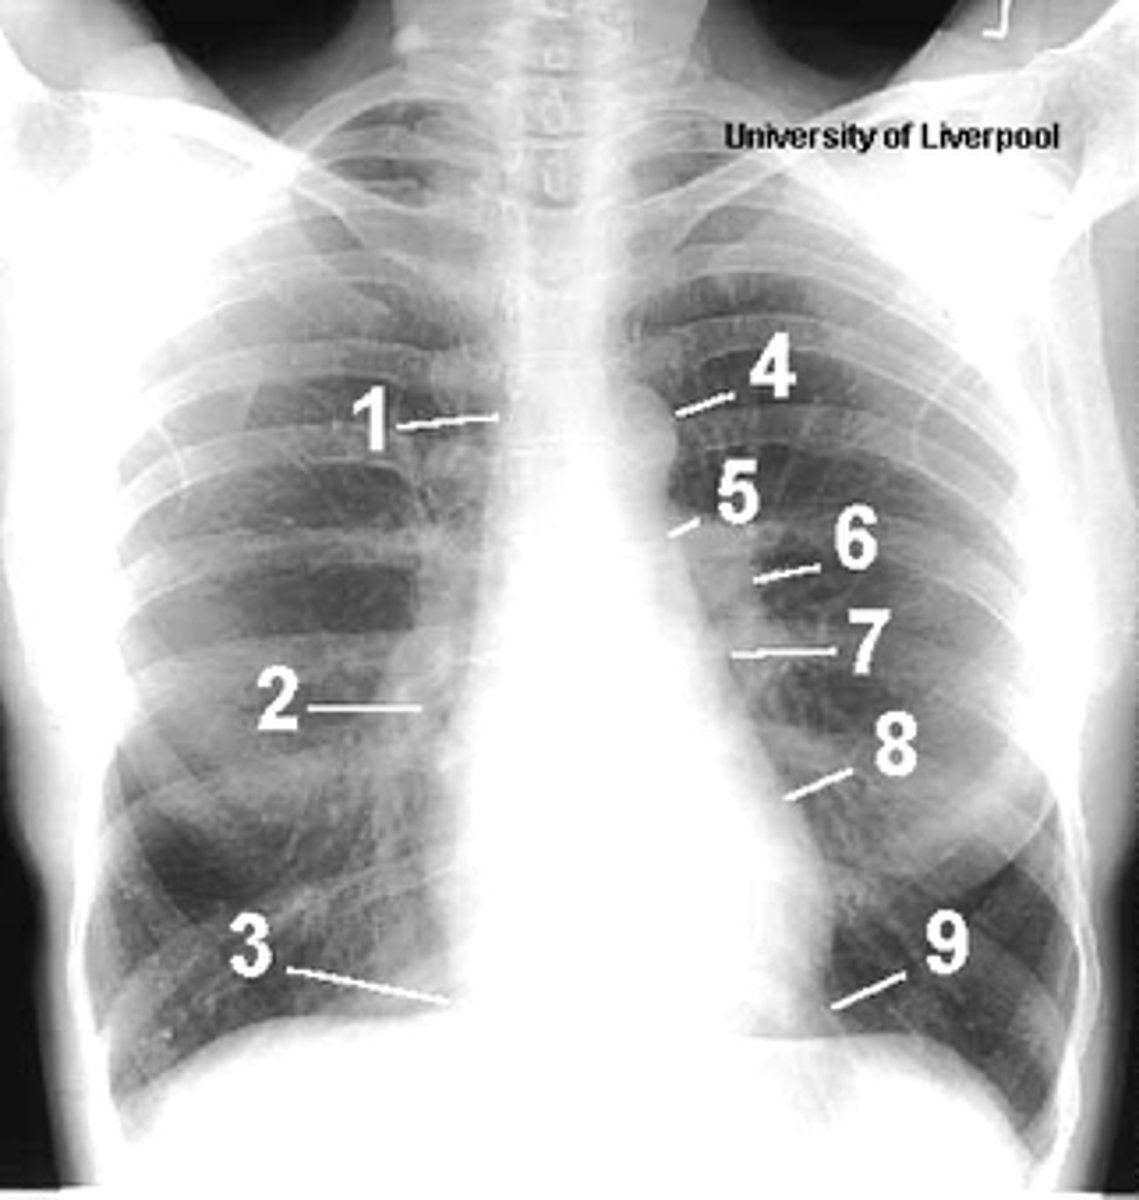

1

superior vena cava

2

right atrium

3

inferior vena cava

4

aortic arch or knob

5

left pulmonary trunk

6

left pulmonary artery

7

left atrium

8

left ventricle

9

left cardiophrenic angle